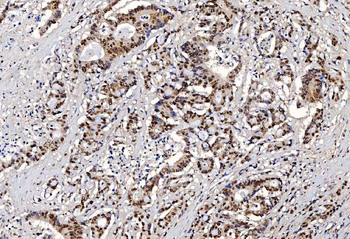

FEN1 Antibody

Catalog Number: orb193665

| Catalog Number | orb193665 |

|---|---|

| Category | Antibodies |

| Description | FEN1 Antibody |

| Clonality | Polyclonal |

| Species/Host | Rabbit |

| Conjugation | Unconjugated |

| Reactivity | Human, Mouse, Rat |

| UniProt ID | P39748 |

| Tested applications | IF, IHC, WB |

| Antibody Type | Primary Antibody |

| Storage | Store at -20°C for long term preservation (recommended). Store at 4°C for short term use. |

| Note | For research use only |